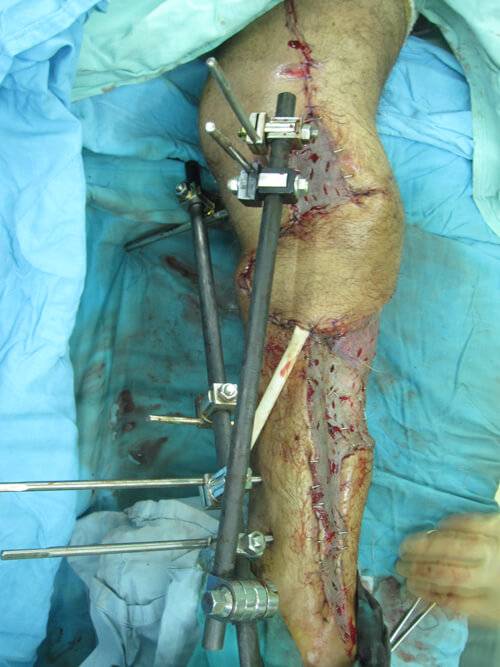

Acute shortening and adjustment of the external fixator was followed by the raising of a fasciocutanteous flap on a single proximal perforator. The flap rotated easily to cover the fracture site. The donor site and any remaining medial and lateral soft tissue wounds were closed using SSG (Figure 11).

Figure 11: Medial, proximally based perforator-plus flap is used to cover exposed bone after thorough

debridement, washout and bone shortening. Skin graft covers the flap donor site and lateral wound.

Three months from this salvage there were no signs of osteomyelitis yet (Figure 12). There was no motor or sensory neural recovery. Regular follow-up and monitoring continue. The surgery has afforded the patient time to consider his options whilst the full debridement prevented imminent sepsis. If the boy elects to keep this limb, the function will always be poor and not consistent with the mobility a 17-year-old should enjoy whatever reconstructive options are applied. Amputation, good rehabilitation and a good prosthesis would give him superior mobility.

Figure 12: Appearance of leg three months from salvage surgery and bone shortening.